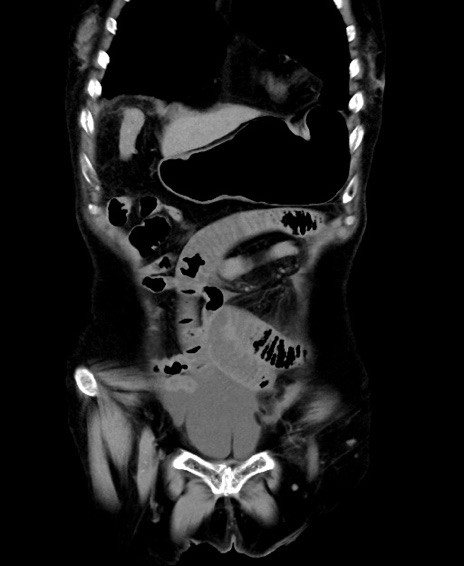

症例40(冠状断像)他院1日前

【症例】90歳代女性

【主訴】腹痛・嘔吐

【現病歴】 食欲低下、嘔吐があり昨日他院受診。肺炎と診断され入院となる。入院後より腹部全体に圧痛あり。胃管留置され経過みていたが、症状持続するため、

当院転院となる。

【既往歴】胸椎圧迫骨折、胆石症

【身体所見】腹部:中央に激痛あり、圧痛あり、反跳痛不明

【データ】WBC 17100、CRP 18.82

横断像